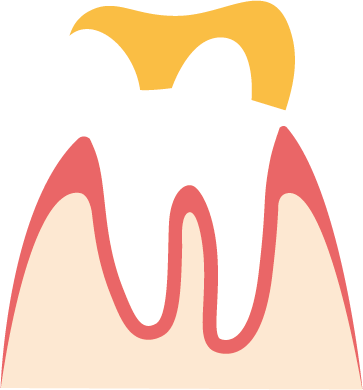

Teilkrone